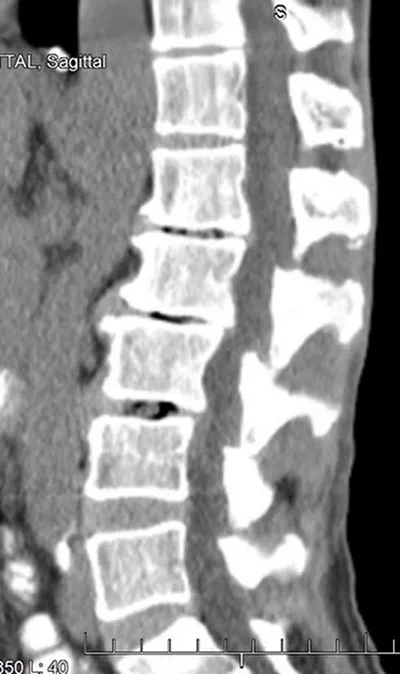

Section titled “Pain in the Hip”To give another example, here's the CT of a heavy equipment operator's hip joint.

The heavy equipment operator

On the upper left is the pelvic bone with its socket-style hip joint. Rising from the lower right is the top of the femur with its ball fitting into the socket.

The radiologist read this as irregular contour of the acetabular (hip) joint, with mild to moderate osteoarthritis.

In English, this means that both the ball at the top of the femur and the socket in the pelvic joint, which should have smooth surfaces, do not.